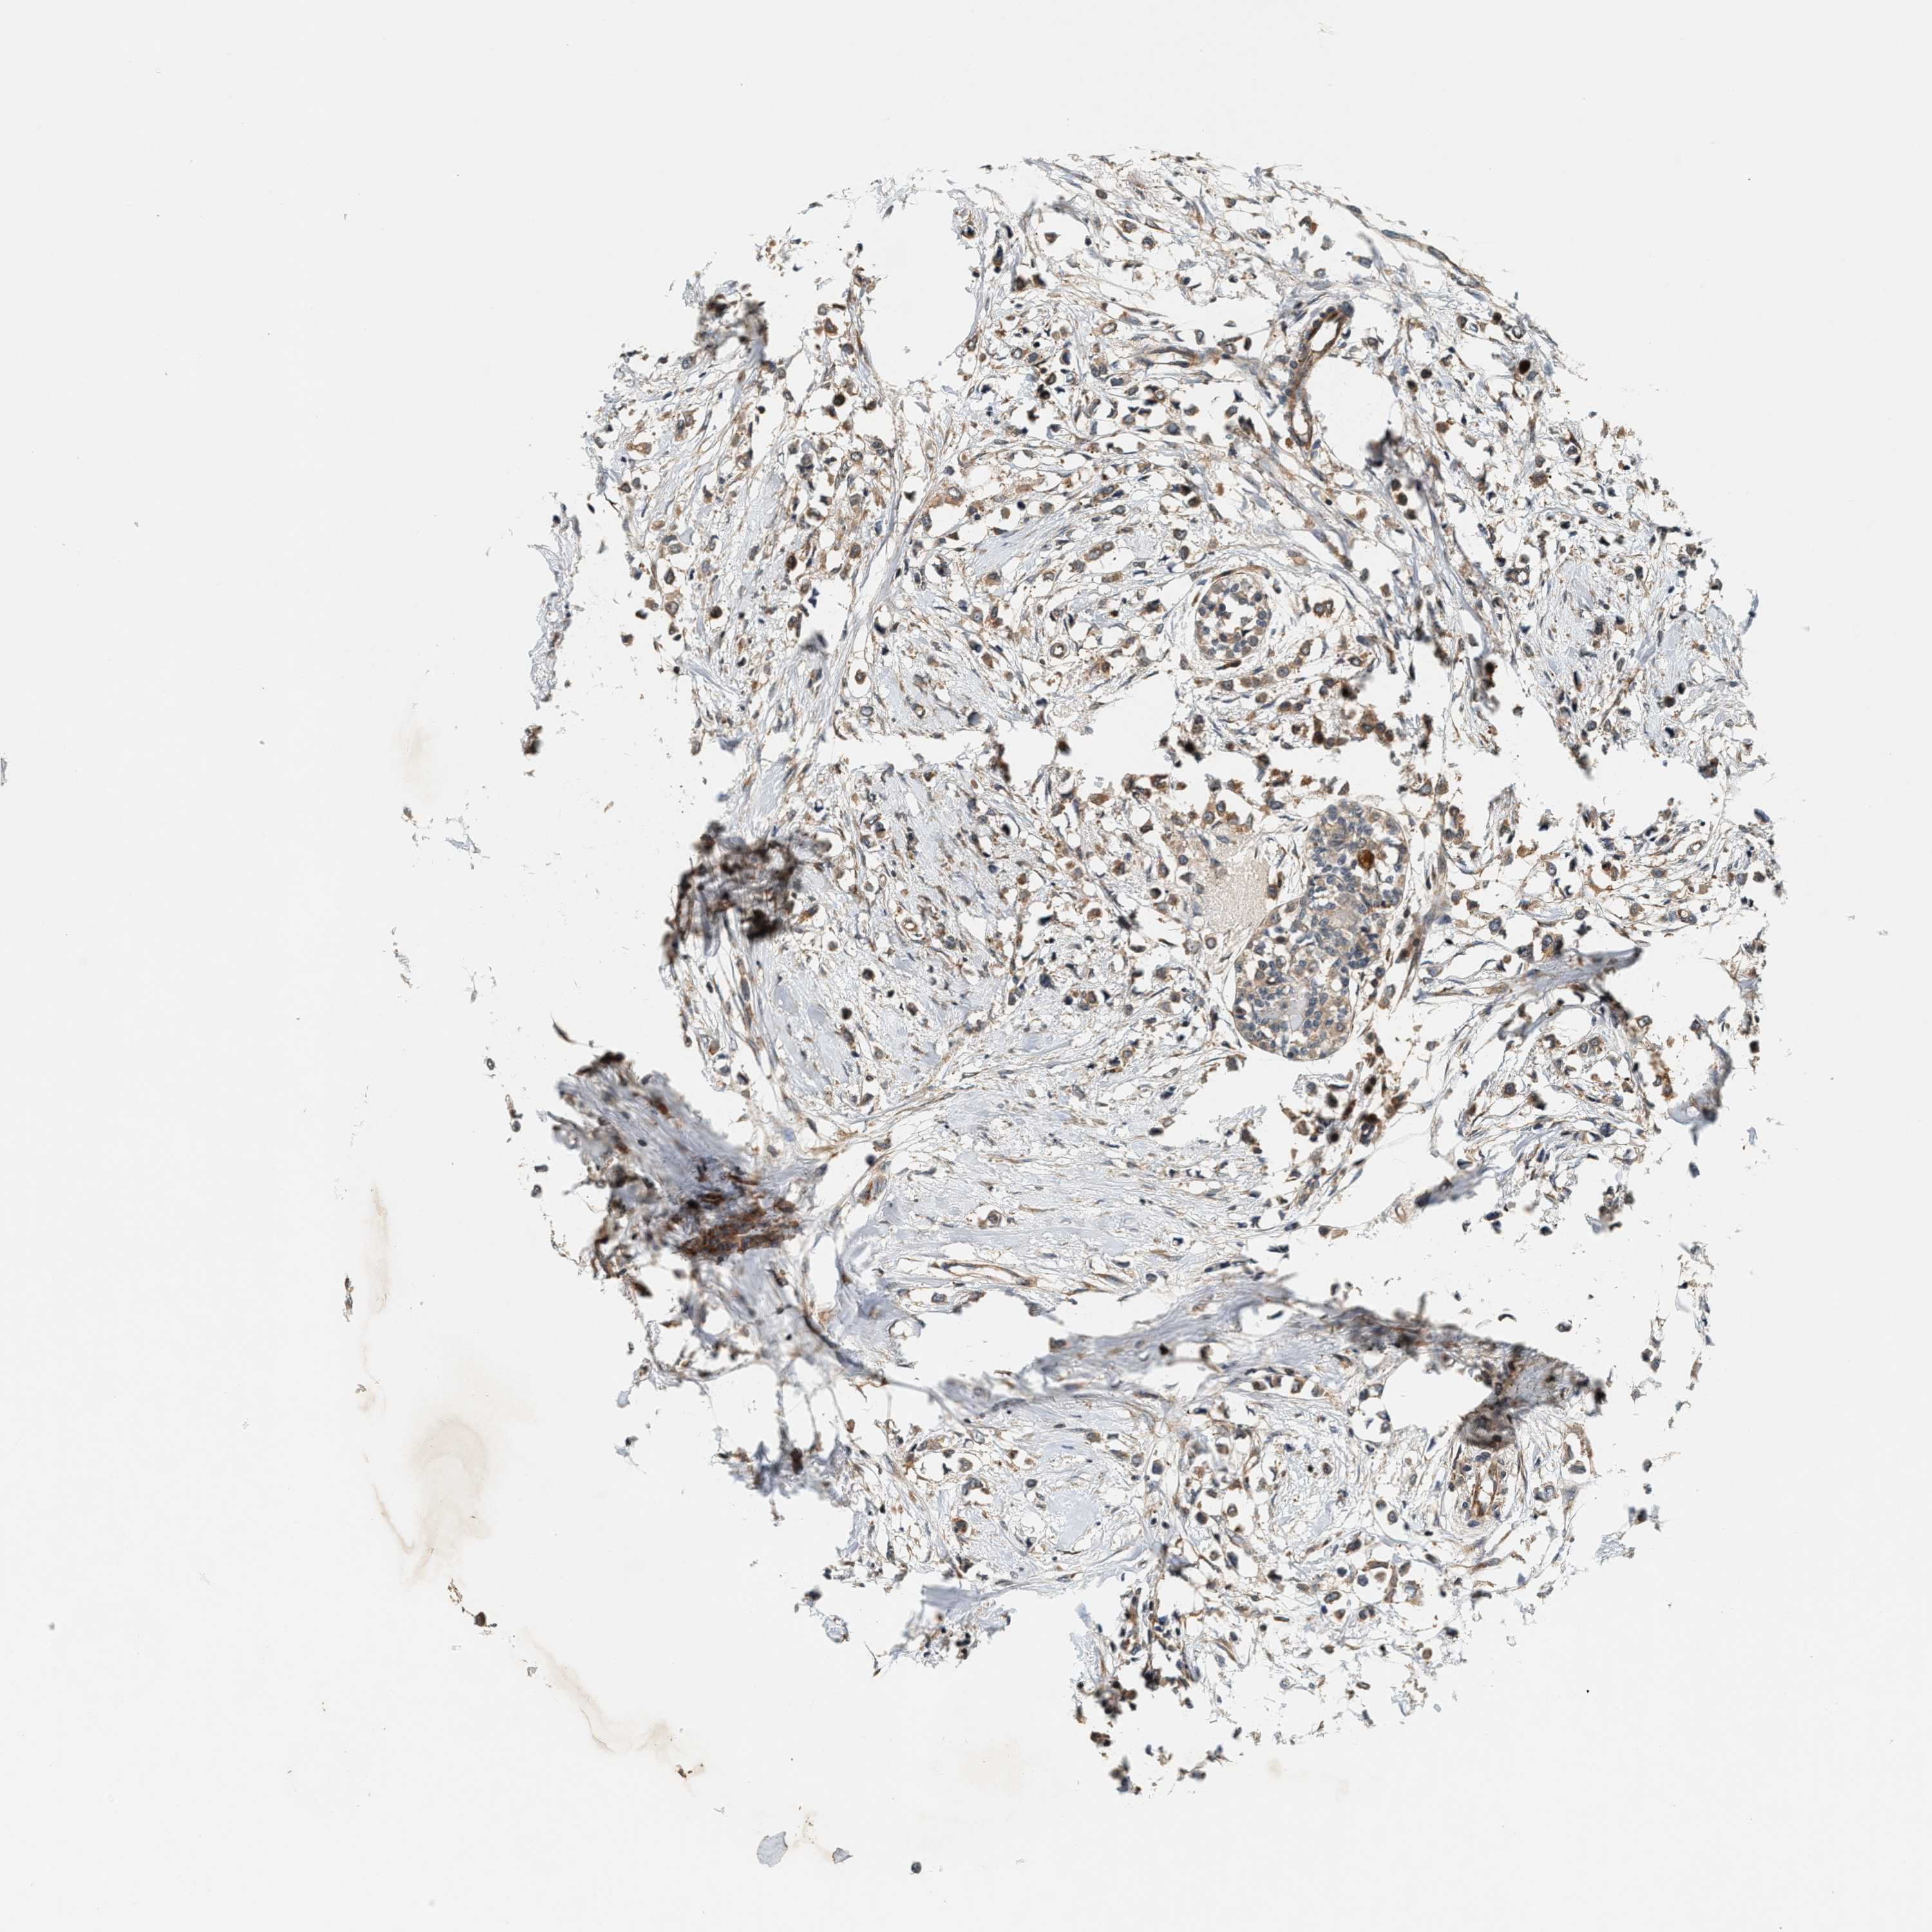

CANCER BREAST CANCER Show tissue menu

BRCA TCGA BRCA VALIDATION PROTEIN EXPRESSION

ANTIBODIES

AND

VALIDATION